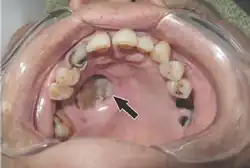

Tissue destruction of inside upper mouth

Should the fungus deposit in the nose or sinus and extend to brain, symptoms and signs may include one-sided face pain or headache.[7] There can be numbness, fever, loss of smell, a blocked nose or runny nose.[7] The person may appear to have sinusitis.[23] The face may look swollen on one side, with rapidly progressing "black lesions" across the nose or upper inside of mouth. One eye may look swollen and bulging, and vision may be blurred.[5][23][24]

Fever, cough, chest pain, and difficulty breathing, or coughing up blood, can occur when the lungs are involved.[5] A tummy ache, nausea, vomiting and bleeding can occur when the gastrointestinal tract is involved.[5][25] Affected skin may appear as a dusky reddish tender patch with a darkening centre due to tissue death.[26] There may be an ulcer and it can be very painful.[4][6][26]